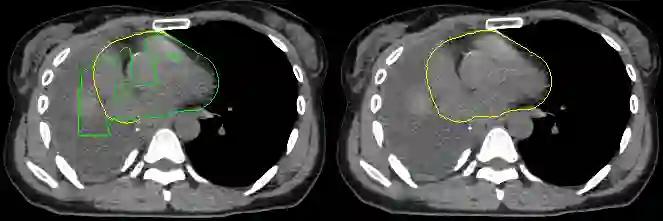

Organ-at-risk contouring is still a bottleneck in radiotherapy, with many deep learning methods falling short of promised results when evaluated on clinical data. We investigate the accuracy and time-savings resulting from the use of an interactive-machine-learning method for an organ-at-risk contouring task. We compare the method to the Eclipse contouring software and find strong agreement with manual delineations, with a dice score of 0.95. The annotations created using corrective-annotation also take less time to create as more images are annotated, resulting in substantial time savings compared to manual methods, with hearts that take 2 minutes and 2 seconds to delineate on average, after 923 images have been delineated, compared to 7 minutes and 1 seconds when delineating manually. Our experiment demonstrates that interactive-machine-learning with corrective-annotation provides a fast and accessible way for non computer-scientists to train deep-learning models to segment their own structures of interest as part of routine clinical workflows. Source code is available at \href{https://github.com/Abe404/RootPainter3D}{this HTTPS URL}.